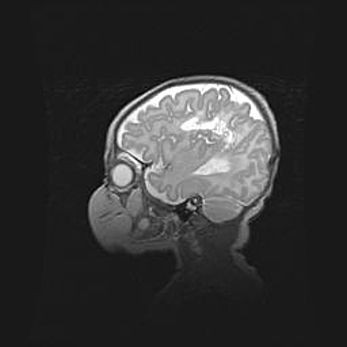

Церебральная ишемия II.

Возраст: 5 дней

Вес: 3400 г

Пол: женский

Окружность головы: 35 см

Срок гестации: 39 недель

Церебральная ишемия – это заболевание, характеризующееся недостаточностью (гипоксией) либо полным прекращением (аноксией) снабжения мозга кислородом по причине закупорки одного или нескольких сосудов. Это приводит к  что метаболическим расстройствам различной степени тяжести в тканях головного мозга, развитию коагуляционных некрозов и гибели нейронов.